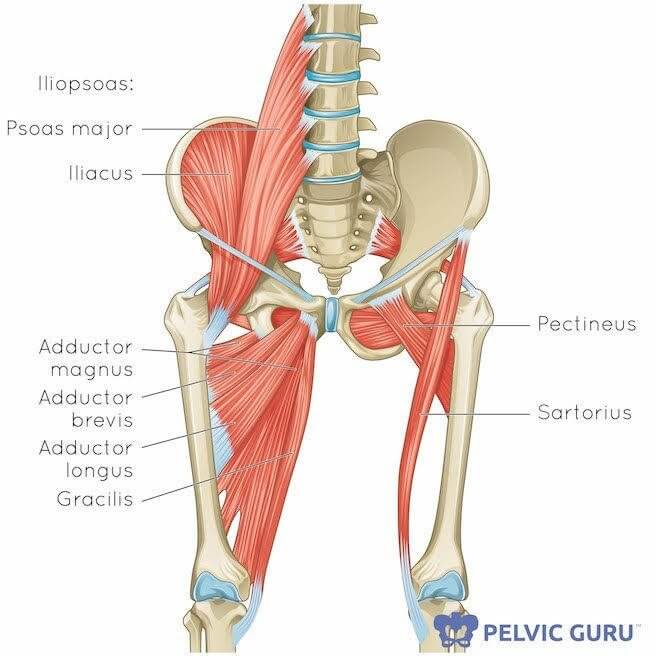

Анатомия и Функции Мышцы Adductor Magnus